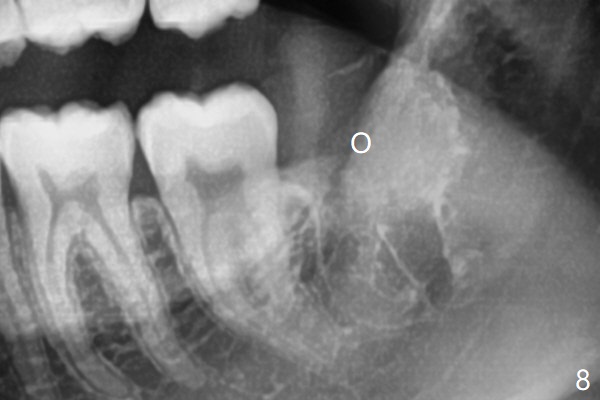

A 19-year-old man returns for #1,16,17 and 32 extraction (Fig.1,2). Because of horizontal impaction of #32 and no bone #31 distal post extraction (Fig.3 *), 3D bond (.5 cc) will be placed in the mesial socket of #32 (Fig.4 red), while Osteogen plug (1/2 (O)) in the distal one. Since there is no bony defect between #17 and 18 after extraction (Fig.5 *), a piece of Osteogen plug (cut half apical) will be inserted in #17 socket, whereas 2 small pieces of Osteogen plug placed in the apical portions (triangle and spindle shaped). Take posterior panoramic X-ray postop (bitewing type, CT format, not XV). There appears bone formation in the socket 5 months postop (Fig.10,11).

Since #32 sockets seem large, extending mesiobuccal (Fig.6), Bond Apatite (1 cc) is placed instead (Fig.7 B), covered by 1/3 of Osteogen plug (O) and sutured with 4-0 PGA. Extraction of #17 is also difficult. As 2 sockets are indistinct, a piece of Osteogen plug with split is placed (Fig.8) upside down (Fig.9 vs. Fig.5). There appears bone formation in the socket 5 months postop (Fig.10,11).